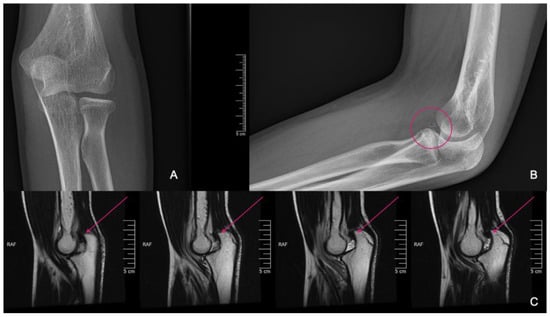

An 11-year-old girl reported to our infirmary on the 10 October 2020 with recurrent posterior subluxation of the elbow. The patient’s history described a previous injury in 2017 when she jumped from a swing and ended up injuring her left elbow (Figure 1). This luxation injury was reduced and treated conservatively with a cast for six weeks. In 2018, she suffered another injury on the same extremity, which was treated the same way. In April 2019, her elbow dislocated three times in a single day, so a cast was applied for seven weeks, and X-rays and CT scans were performed.

Figure 1.

Plain radiographs taken at the initial injury.

Figure 2.

CT images were provided for surgical planning; the defect can be seen highlighted in the pink circle.

Imaging of the posterior dislocation at age 13, image (A) showing the luxation upon ebow extension and (B) from a lateral view in flexed position.

He suffered another elbow trauma due to a fall at the age of 14, resulting in pain and dislocation. X-rays showed no recent fracture, but a 5 mm rounded bone fragment was visible. MRI was requested for diagnostic purposes and further exploration (Figure 6). The results indicated that the fragment originated from the coronoid process and that the elbow was in a dorsally subluxated position. With regard to the instability, the exploration of the joint with debridement and reconstruction was proposed. A CT scan was performed for surgical planning, which yielded equivalent results to the MRI. A summary of events can be seen in Table 2.

Figure 6.

X-rays showing fragmentation, highlighted by the pink circle (A,B). Subluxation is visible on the MRI pointed at with pink arrows (C).